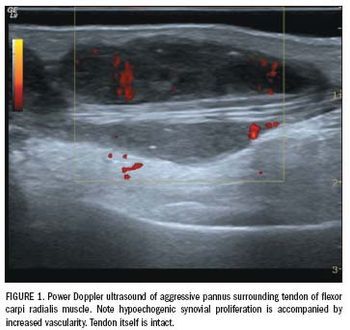

Rheumatoid arthritis is a chronic and progressive inflammatory disease of the joints.

Rheumatoid arthritis is a chronic and progressive inflammatory disease of the joints. It affects approximately 1% of the general population, with incidence being three times higher in women than men.